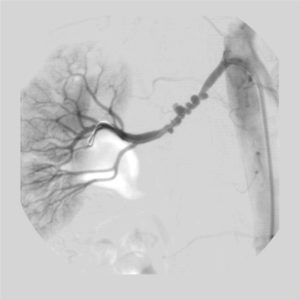

Usually patients who present with otherwise unexplained artery dissection or visceral artery aneurysm will undergo further imaging. This imaging should probably include a CT or MR angiogram of the brain, neck, chest, abdomen and pelvis. The purpose of such imaging is to detect typical disease patterns and also to assess the extent of disease. It is not uncommon for such imaging to result in evidence of dissection in other, asymptomatic, vascular beds. For example, a patient presenting with carotid artery dissection may be found to have renal infarctions she has never known she had and perhaps also even spontaneous coronary artery dissection (SCAD). Patients with fibromuscular dysplasia should be screened for intracranial aneurysms.

Even when fibromuscular dysplasia is given as the diagnosis, I have seen many cases when I disagreed. Many colleagues of mine who treat FMD patients have a similar experience. Specifically, it is also important to avoid making a diagnosis based solely on dissected arteries (as a dissection may result in morphological changes in the artery that could result in errors in diagnosis). Thus, another reason to get systemic imaging is to find other, non-dissected, but diseased arteries that can clarify the diagnosis.